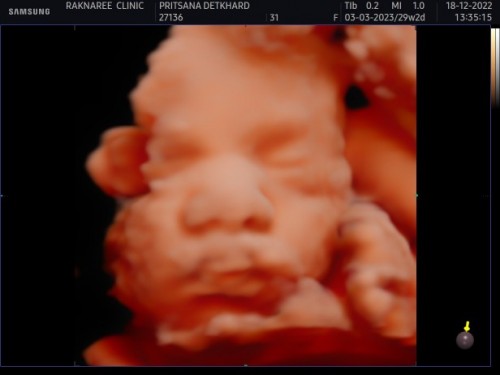

ซาว4มิติ ตอน27สัปดาห์ หมอบอกน้องหนัก1152คะ น้องเล็กไปไหมคะ ตอนนี้แม่จะเข้า32สัปดาห์แล้วคะ กังวนน้องจะตัวเล็ก

บ้านนี้29วิคน้อง1028เองค่ะ รอมกราไปซาวใหม่ค่ะ